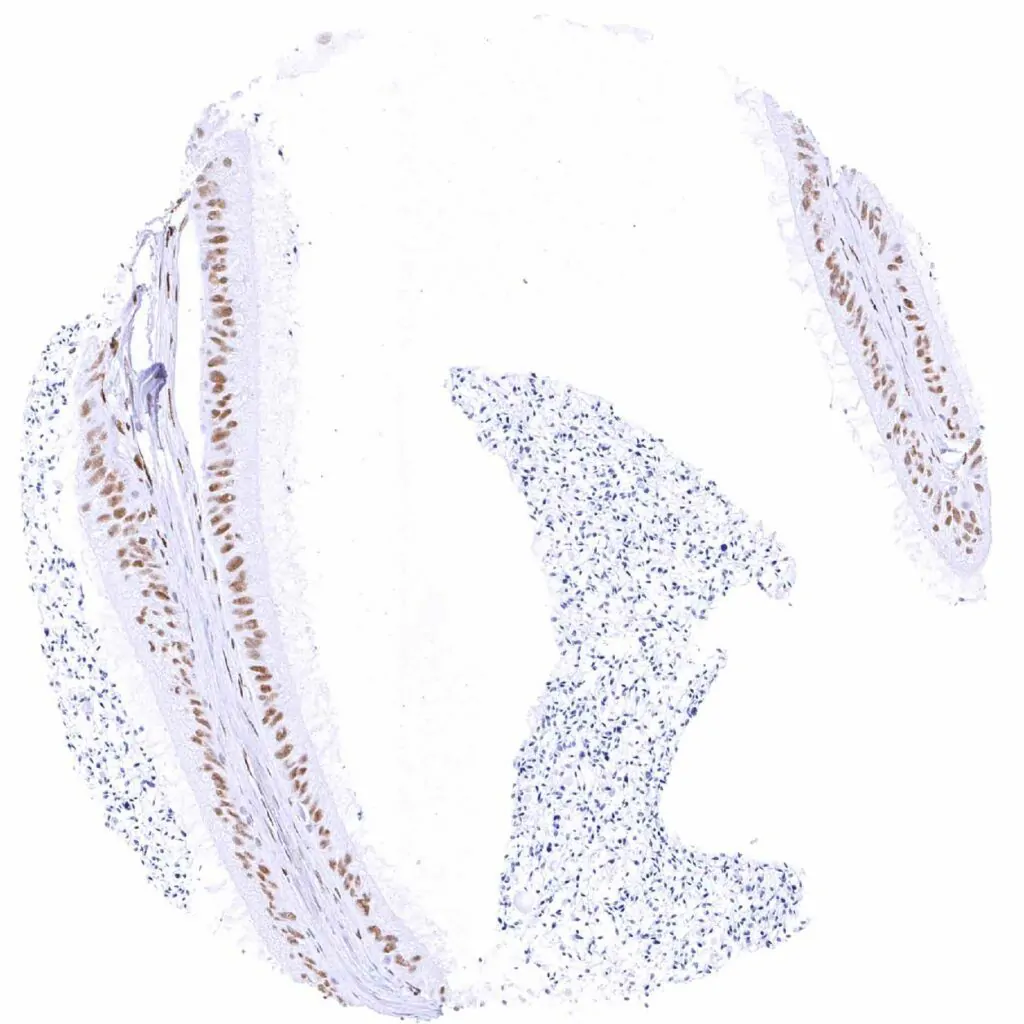

Esophagus, squamous epithelium – Weak TLE1 staining of a subset of lymphocytes and of the squamous epithelium, predominantly of the suprabasal cell layers